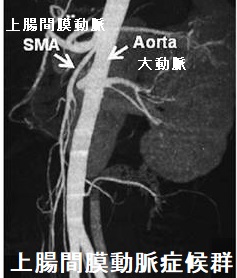

甲状腺機能亢進症/バセドウ病で上腸間膜動脈症候群(ウィルキー症候群:Wilkie 症候群)を引きおこした症例が報告されています(The journal of the Japan Surgical Association 65, 2055-58, 2004)(Medicine (Baltimore). 2020 Nov 13;99(46):e22664.)。

上腸間膜動脈症候群とは、大動脈と上腸間膜動脈に十二指腸水平部が挟まれて通過障害をおこした状態です。嘔吐や腹部膨満感などの腸閉塞症状を来します。甲状腺機能亢進症/バセドウ病では、代謝が亢進して内臓脂肪が分解され、大動脈と上腸間膜動脈の隙間が狭くなるのが原因と考えられます。

病気でなくても、ダイエット目的で甲状腺ホルモン剤(レボチロキシン)過剰服用し、上腸間膜動脈症候群(ウィルキー症候群:Wilkie 症候群)を来した報告もあります(Rev Gastroenterol Peru. 2020 Jul-Sep;40(3):274-277.)。